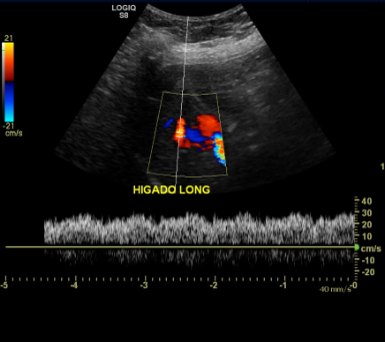

• LESIÓN HEPÁTICA, MULTILOBULADA, ANECOGÉNICA CON REFUERZO POSTERIOR EN EL LÓBULO DERECHO.

• VASCULARIZADA AL DOPPLER COLOR

• EN DOPPLER ESPECTRAL, PRESENTA FLUJO TURBULENTO, PRINCIPALMENTE ANTERÓGRADO, QUE SUGIERE PROVENIR DE UNA RAMA DE LA VENA PORTA.

• VENA PORTA NO PRESENTA ANOMALIAS